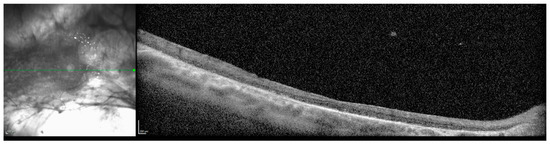

Figure 4.

Optical coherence tomography (OCT) of macula, 8 months following pars plana vitrectomy with scleral buckle procedure, right eye, age 32. The vitreous hemorrhage had cleared, and the macula was flat. Resolution was poor due to nystagmus.

The patient continued to attend surveillance appointments for the next decade with a relatively stable clinical course. Next generation sequencing and Sanger sequencing of the KIF11 gene and flanking introns performed in consultation with a medical geneticist revealed a previously undocumented, heterozygous de novo c.210+2del intronic variant of the KIF11 gene (Prevention Genetics, 2017, Marshfield, WI, USA, NM_004523.3). The patient’s biological parents and two siblings declined clinical examination and genetic testing for the variant. At age 32, a small right vitreous hemorrhage was identified, and there was concern for progression and temporal foveal encroachment of the patient’s chronic RD (Figure 3). The patient underwent a right scleral buckle procedure with external drainage, limited pars plana vitrectomy, cryoretinopexy, and intravitreal injection of SF6 gas. Following postoperative recovery, visual acuity in the right eye improved to 20/200 from a baseline of 20/400, and the macula and fovea remained attached (Figure 4).